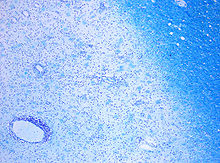

The name multiple sclerosis refers to the scars (sclerae – better known as plaques or lesions) that form in the nervous system. MS lesions most commonly involve white matter areas close to the ventricles of the cerebellum, brain stem, basal ganglia and spinal cord; and the optic nerve. The function of white matter cells is to carry signals between grey matter areas, where the processing is done, and the rest of the body. The peripheral nervous system is rarely involved.

More specifically, MS destroys oligodendrocytes, the cells responsible for creating and maintaining a fatty layer—known as the myelin sheath—which helps the neurons carry electrical signals (action potentials). MS results in a thinning or complete loss of myelin and, as the disease advances, the cutting (transection) of the neuron's axons. When the myelin is lost, a neuron can no longer effectively conduct electrical signals. A repair process, called remyelination, takes place in early phases of the disease, but the oligodendrocytes cannot completely rebuild the cell's myelin sheath. Repeated attacks lead to successively fewer effective remyelinations, until a scar-like plaque is built up around the damaged axons. Different lesion patterns have been described.